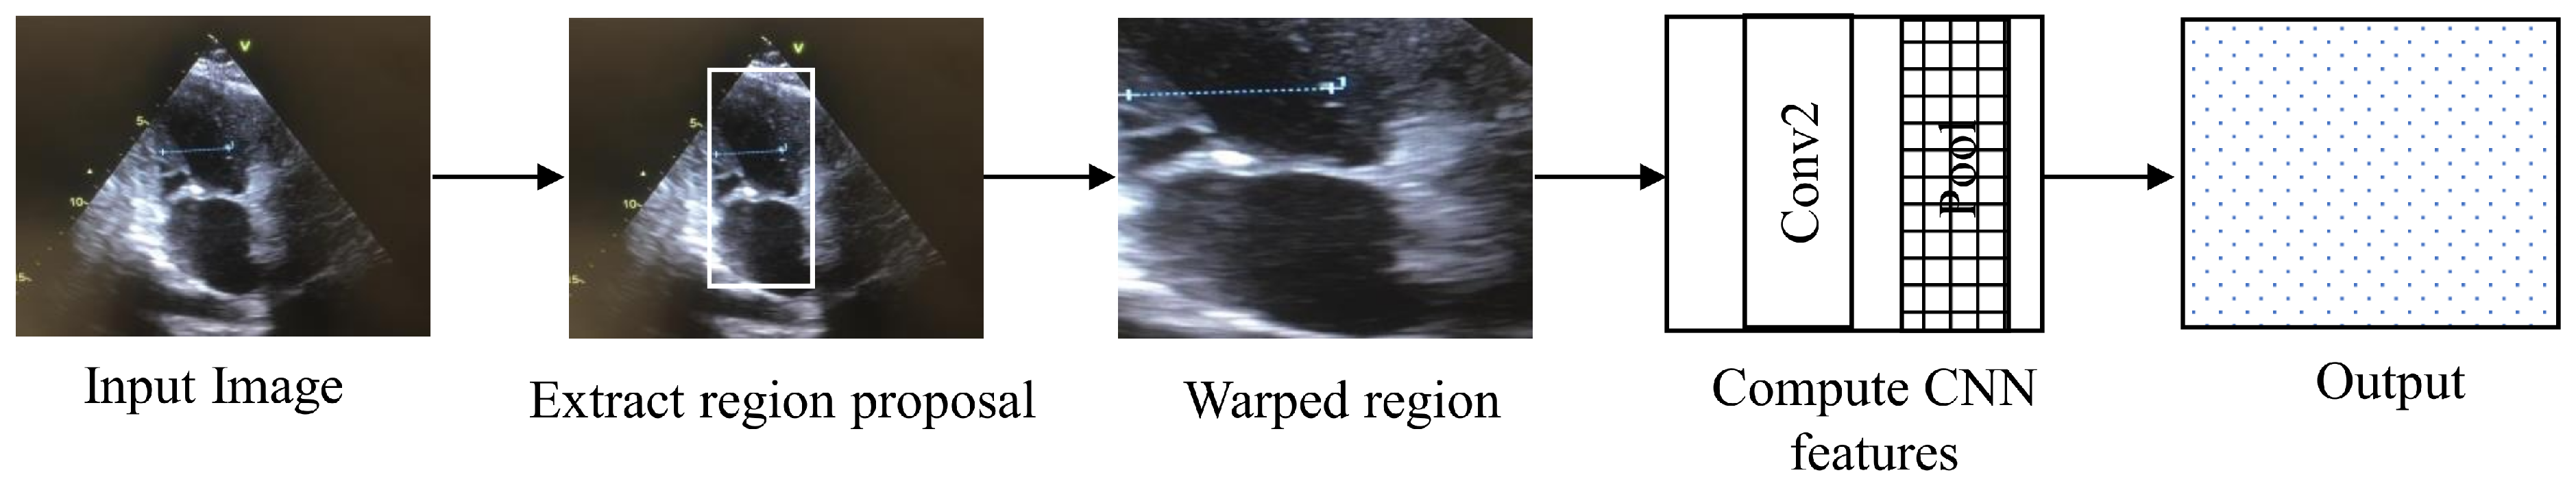

4.4. Regions with CNN Features

Regions with CNN features (RCNN) is an architecture used for segmentation and object detection. RCNN is called region-based because the input is divided into several regions to detect the object of interest, as shown in the Figure 6 [21]. RCNN takes around 45 s for processing per video frame, making it unsuitable for real-time application.

Figure 6.

The architecture of regions with CNN features.